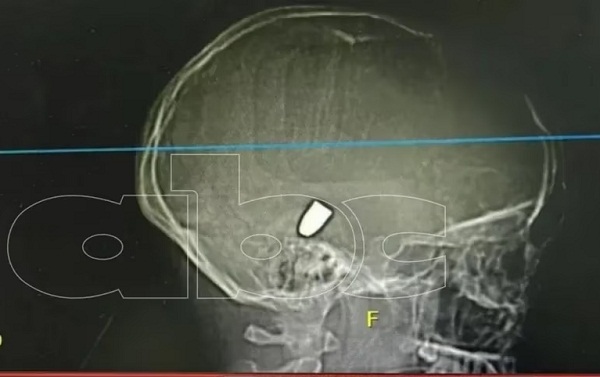

Una menor fue llevada por sus padres en la noche del sábado, al hospital del Instituto de Previsión Social (IPS) en Pedro Juan Caballero, ya que la misma convulsionaba sin aparente razón, pero luego de haber sido trasladada a Asunción se le realizó una tomografía y detectaron que una bala se incrustó en el cráneo de la adolescente.

Tras el hallazgo, la víctima fue sometida a una cirugía craneal, en la cual los médicos drenaron la zona afectada y mejoraron la condición clínica, sin embargo la bala sigue alojada en la cabeza de la adolescente, de acuerdo al informe de ABC TV.